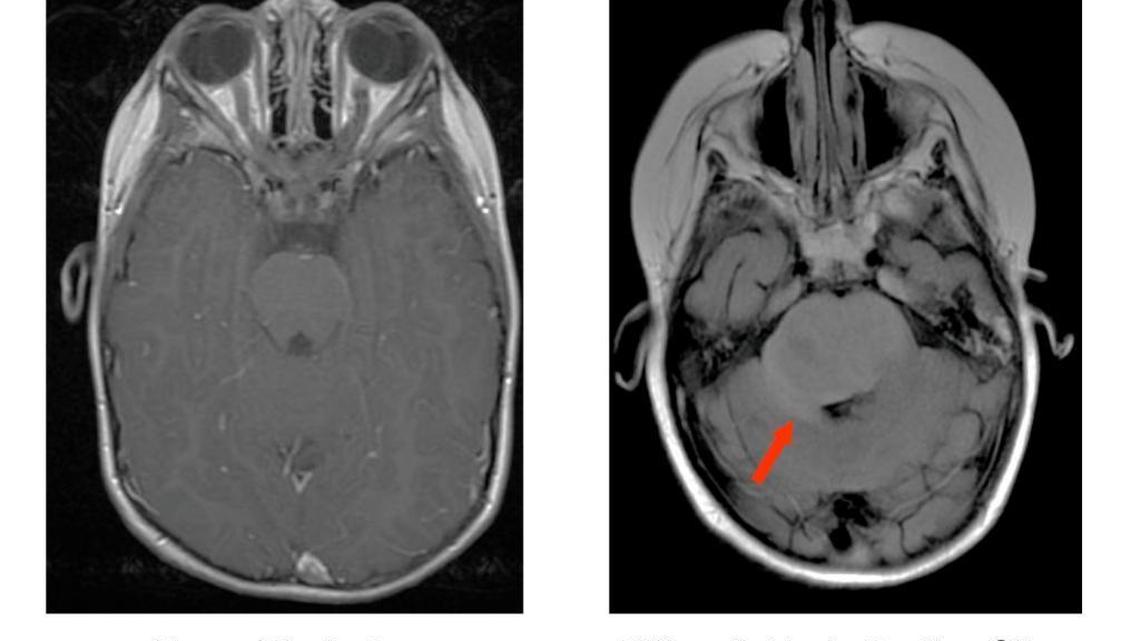

DIPGNobody knows — not even doctors — what causes a rare brain cancer that kills childrenUpdated September 22, 2017 at 1:10 PM